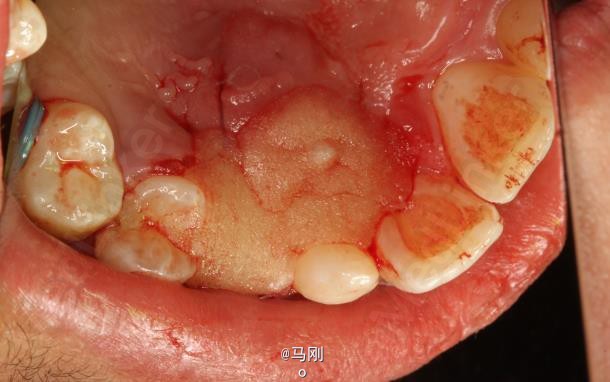

患者、李xx、男、14岁。主诉:牙齿排列不齐,要求正畸治疗。平素体质一般,无药物、食物过敏史,无高血压、心脏病等系统性疾病。

查体 辅查

专科检查:右侧乳尖牙滞留,13腭侧粘膜轻度肿胀。CBCT检查:13位于腭侧。